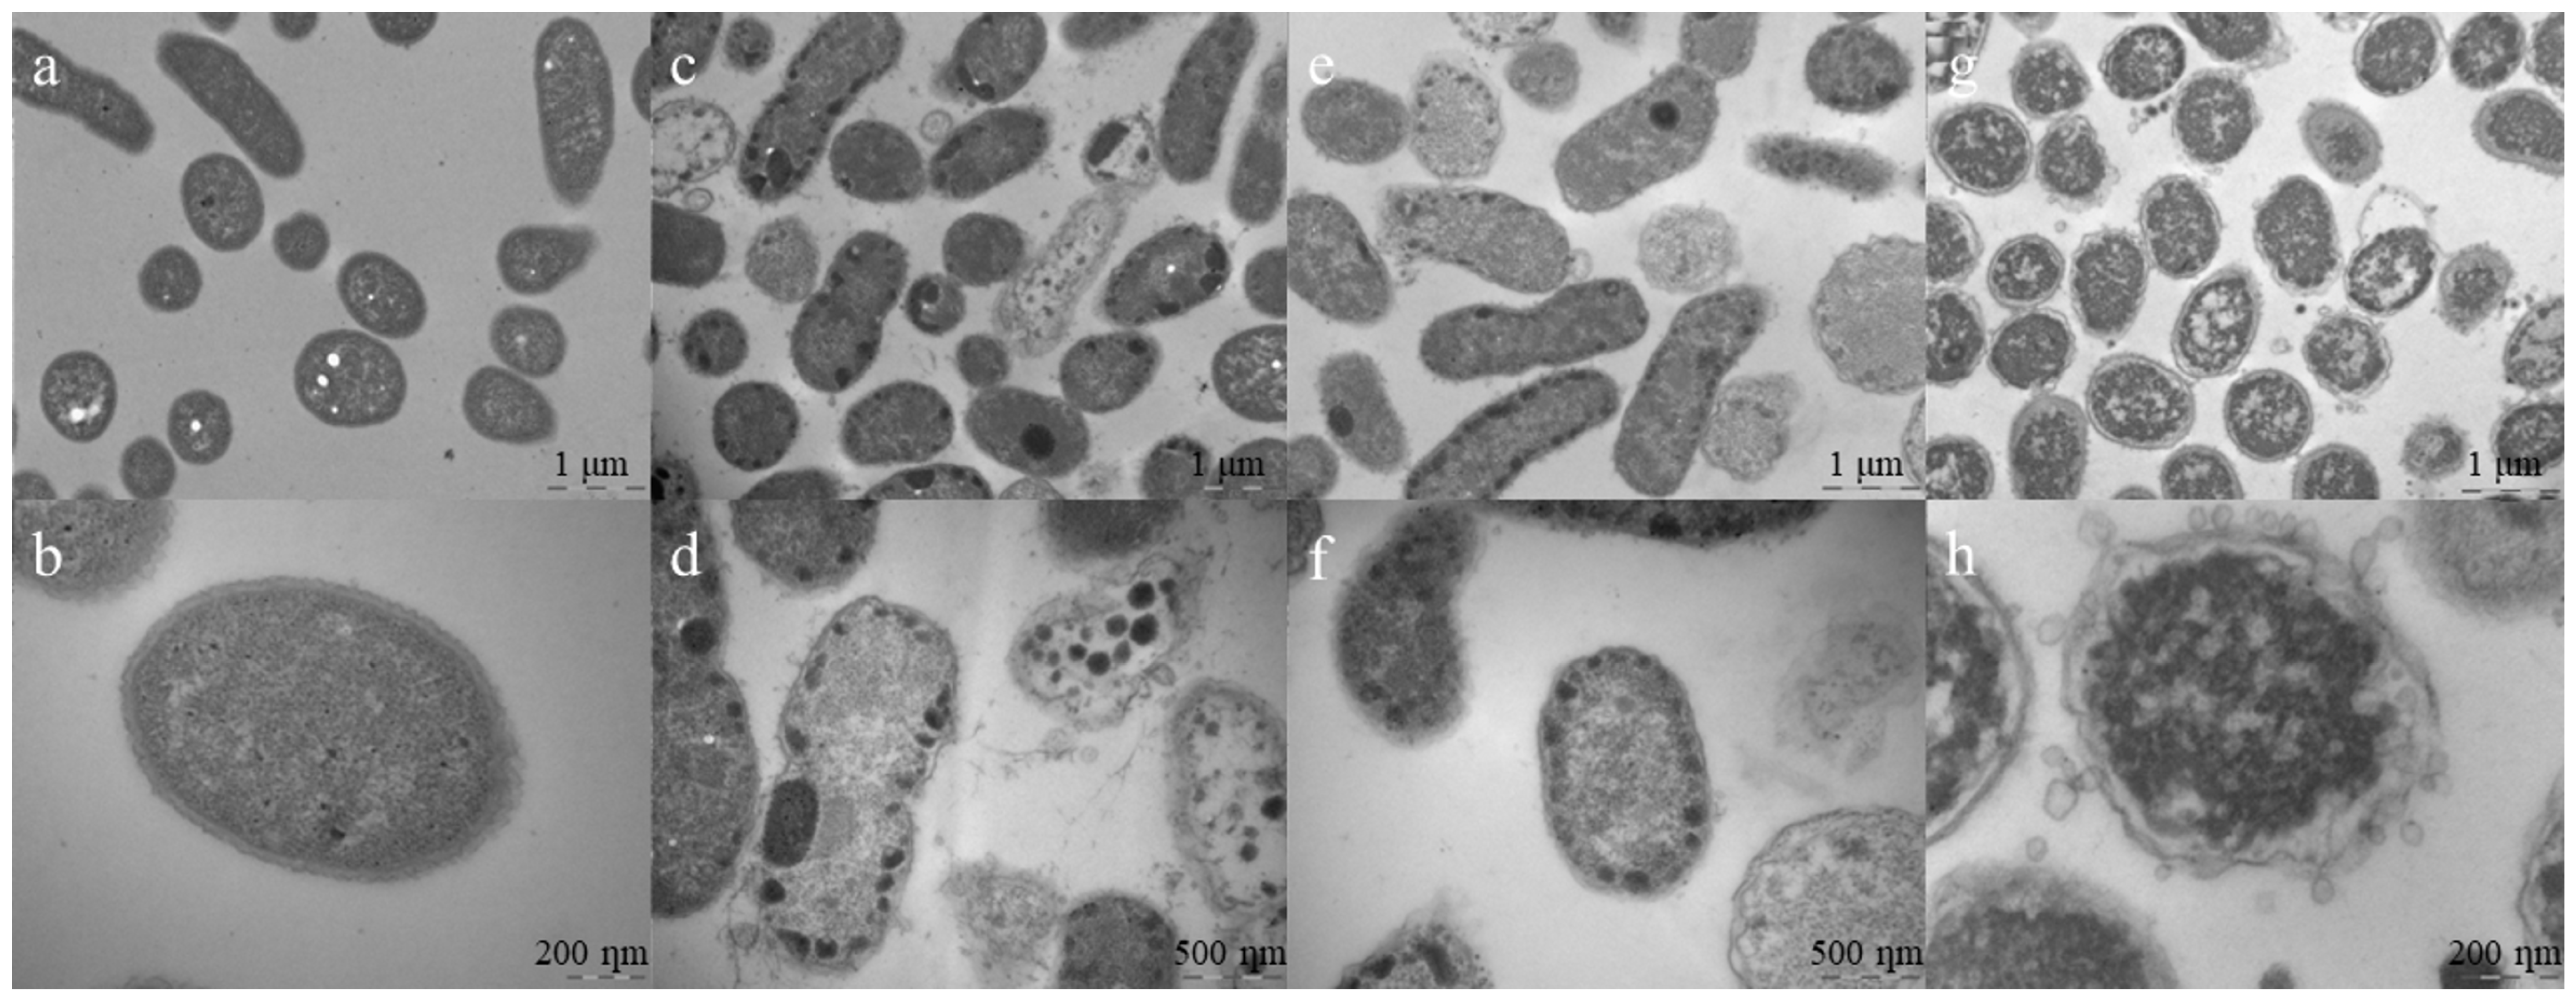

2.7. Transmission Electron Microscopy (TEM)

4.11. Transmission Electron Microscopy